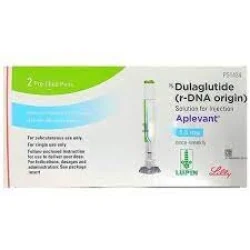

Welcome to Growfirst, your 'one stop shop' where you are assisted with day-to-day and exclusive planning and purchasing activities. We take pride in our iconic customer support number, 8828381880 and the fact that we own a strong hold on local business information pan India. Our service extends from providing address and contact details of business establishments around the country, to making orders and reservations for leisure, medical, financial, travel and domestic purposes. We enlist business information across varied sectors like Hotels, Restaurants, Auto Care, Home Decor, Personal and Pet Care, Fitness, Insurance, Real Estate, Sports, Schools, etc. from all over the country. Holding information right from major cities like Mumbai, Delhi, Bangalore, Hyderabad, Chennai, Ahmedabad and Pune our reach stretches out to other smaller cities across the country too. Our 'Free Listing' feature gives a platform to showcase varied specialities. We then furnish you with the information via phone, SMS, web, App and WAP as well as, create a space for you to share your experiences through our 'Rate & Review' feature. Through the 'Best Deals', 'Last Minute Deals' and 'Live Quotes', we make sure that you are offered the best bargains in the market.